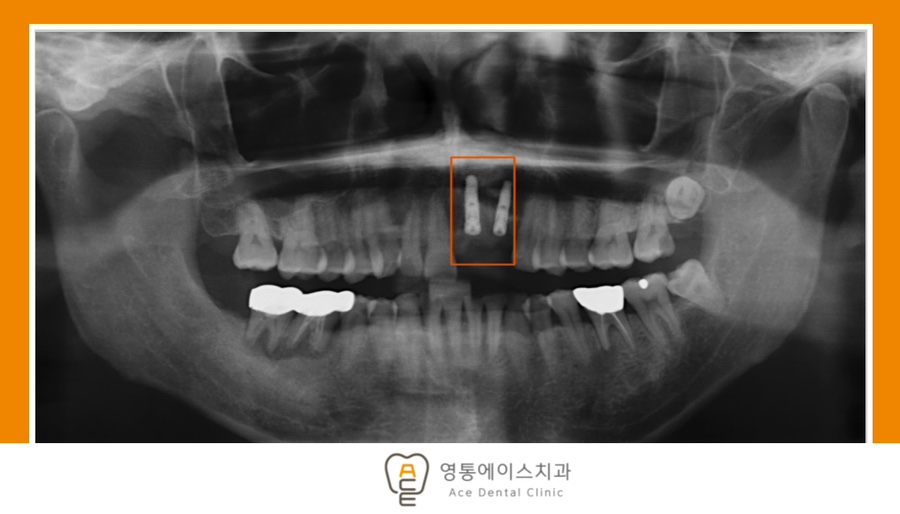

오늘은 부러진 자연 치아를 발치한 후 임플란트를 통해 기능과 심미성을 모두 회복한 사례를 함께 알아보도록 하겠습니다.

치료 전 사진 / 2023.09.21

치료 후 사진 / 2024.01.06

*치료 기간 : 2023.09.21 ~ 2024.01.06